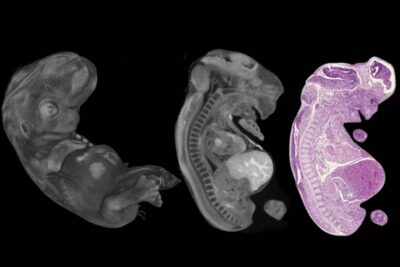

The symposium sections offered 53 scientific presentations, which covered topics ranging from education, female and perinatal pathology, oncology, oncoimmunology and hematology, gastrointestinal pathology, and diagnostic pathology to renal and uroepithelial pathology.